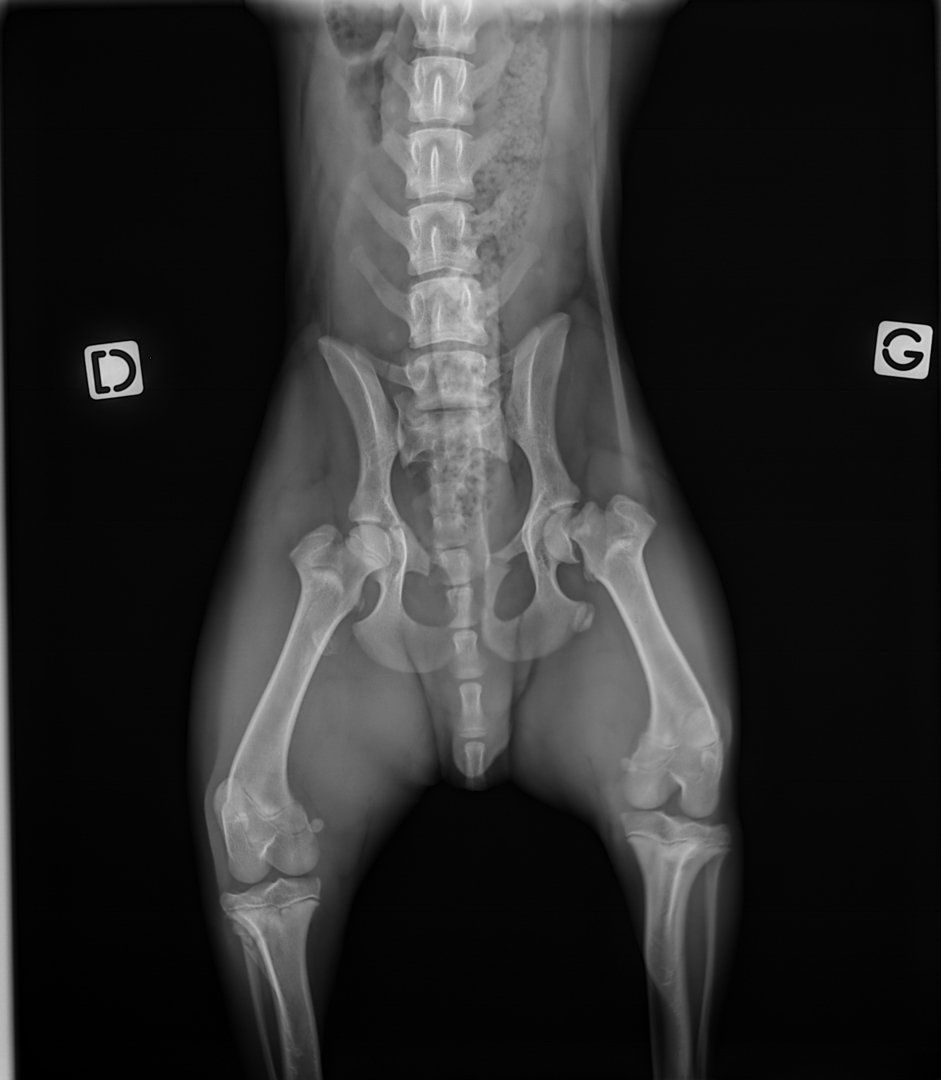

NOUGAT a été opéré de sa fracture fémorale. Les fractures du bassin quant à elles se cicatriseront toutes seules.

A sa présentation au vétérinaire, NOUGAT souffrait de nombreuses plaies d’abrasion, d’une double disjonction sacro-iliaque, d’une fracture pubienne et d’une fracture de Salter Harris de type I de la tête du fémur.

Les disjonctions sacro-iliaques droite et gauche se consolideront par elle-même avec l’observation d’une période de repos. En revanche, une intervention chirurgicale a été nécessaire afin de retirer la tête du fémur. Cela ne posera pas de problème pour sa vie future. Des soins de plaies ont également été faits tous les jours.